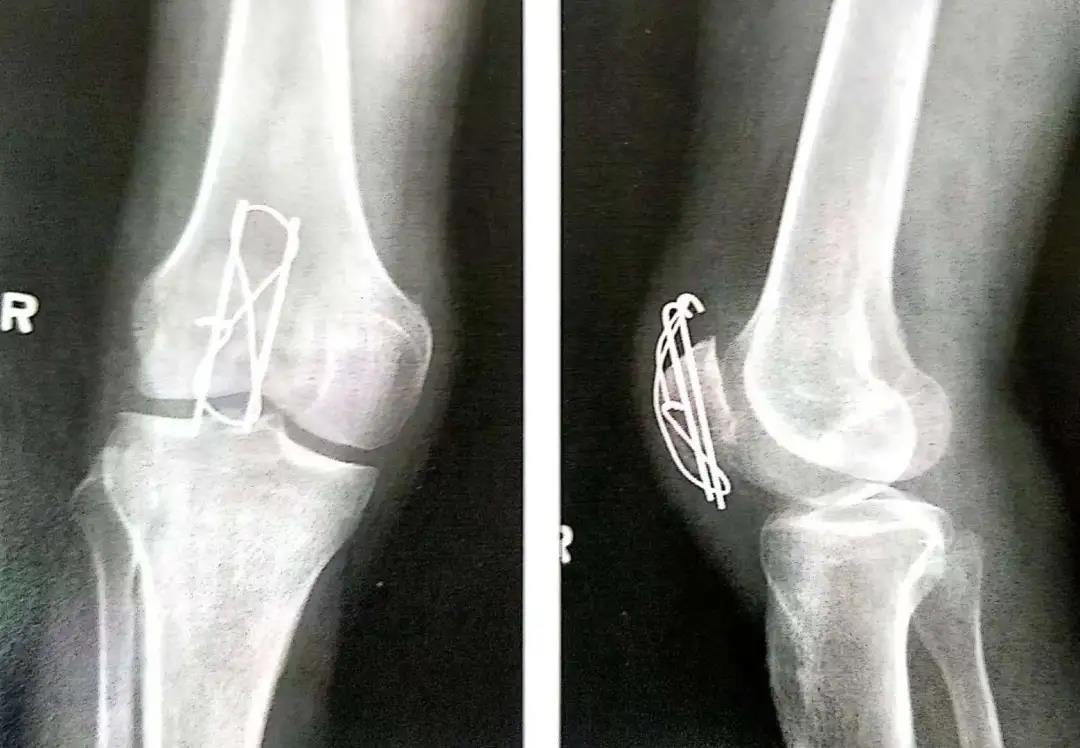

- 钢丝的两端在髌骨前面呈8字形交叉。张力带也可打成非交叉的方式。

- 在直视,触摸或同时借助于术中透视的方式下确保髌骨的关节面达到充分复位,这点非常重要。

- 如果复位满意,用老虎钳在两边慢慢拧紧钢丝。

- 8字形钢丝的内外两边要交替拧紧以使横过骨折端的张力均衡。

- 单侧拧紧会导致不均衡压力,并使环另一边的过度松弛无法恢复。

- 钢丝拧得过紧会导致骨折再次移位或者使骨折进一步加重。